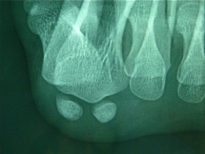

aspect normal en vue axiale |